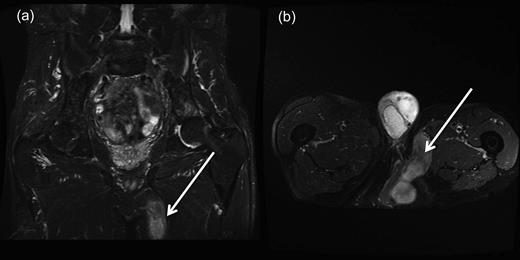

A repeat MRI confirmed a further recurrence of the perineal hernia in the form of uncompromised bowel, which extended beneath the gracilis flap, which then continued into the adductor compartment of the left thigh (Fig. 1a and b).

(a and b) Coronal and transverse magnetic resonance imaging scans demonstrating perineal hernia extending into the left thigh. (Demonstrated by white arrows.)